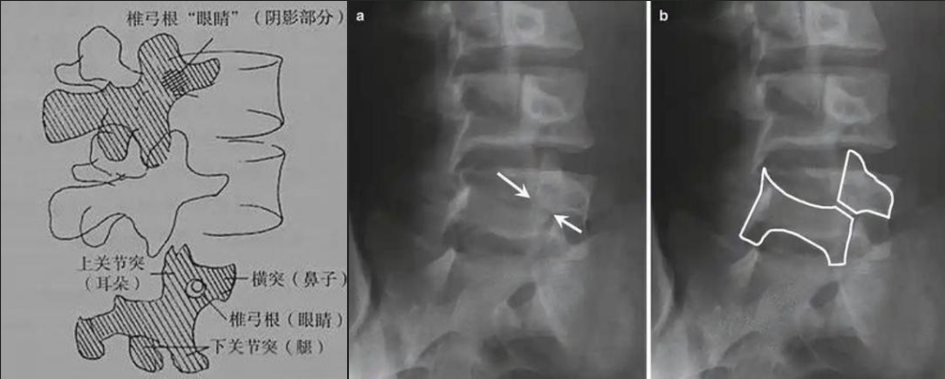

圖a和圖b 腰椎斜位:狗脖“戴項(xiàng)圈征”,診斷椎體椎弓峽部裂

椎弓根峽部是椎體后部椎弓上最狹窄、最薄弱、但應(yīng)力最集中的部位,在常規(guī)腰椎X線正側(cè)位上,因腰椎其他結(jié)構(gòu)的重疊顯示不清,但是在腰椎斜位上,能夠清楚完美地展現(xiàn)出來(lái),若其在斜位片上表現(xiàn)為不連續(xù),則可診斷為椎弓根峽部裂,即腰椎的關(guān)鍵承重部分的骨質(zhì)斷裂,這是導(dǎo)致青少年和運(yùn)動(dòng)員腰痛的主要原因。

在腰椎斜位片上,腰椎的附件結(jié)構(gòu)形成了一個(gè)經(jīng)典的“斯科蒂狗”圖案,其中“狗脖子”處即代表椎弓根峽部,若“狗脖子”上出現(xiàn)了一條透亮清晰的線,就像給狗戴了一條“項(xiàng)鏈”,即“戴項(xiàng)圈征”,這是診斷椎弓峽部裂的直接證據(jù)。